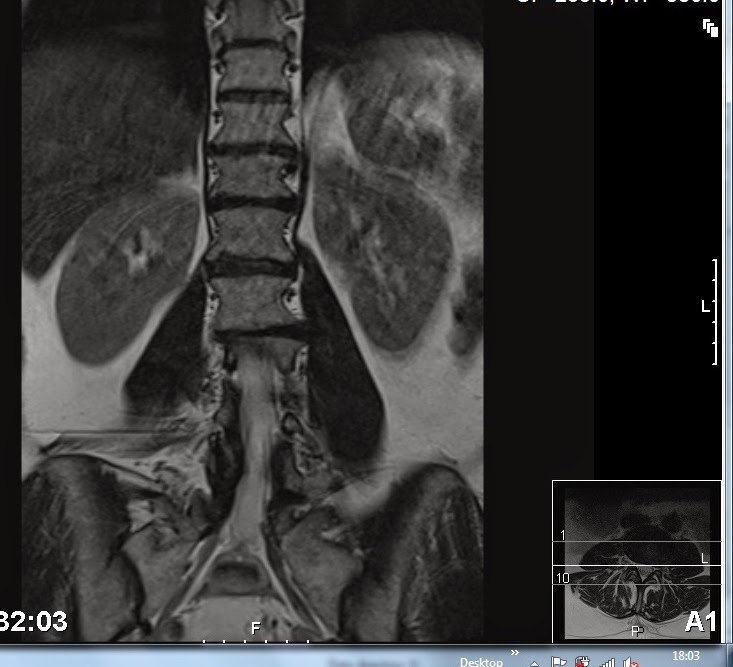

I added my brain scan showed too much white scars and he wasn't sure if I was MS or high Cholestral or high blood pressure. My blood test showed cholesterol higher than normal and I had informed him I changed my diet since. He said he would ask my GP to test regularly.